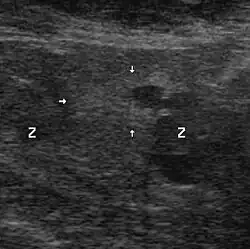

Ultraschall

Genauere Lokalisation und Größenbestimmung erlaubt die Ultraschalluntersuchung (transrektale Sonografie). Tumoren ab zehn Millimeter Durchmesser können damit zuverlässig gefunden werden, kleinere jedoch nur zu etwa 20 %.[54]

HistoScanning ist eine ultraschallbasierte, noch nicht abschließend evaluierte Methode, die jedoch auch wesentlich höhere Sensitivität und Spezifität als gewöhnlicher Ultraschall oder digital-rektale Untersuchungen verspricht.[55]